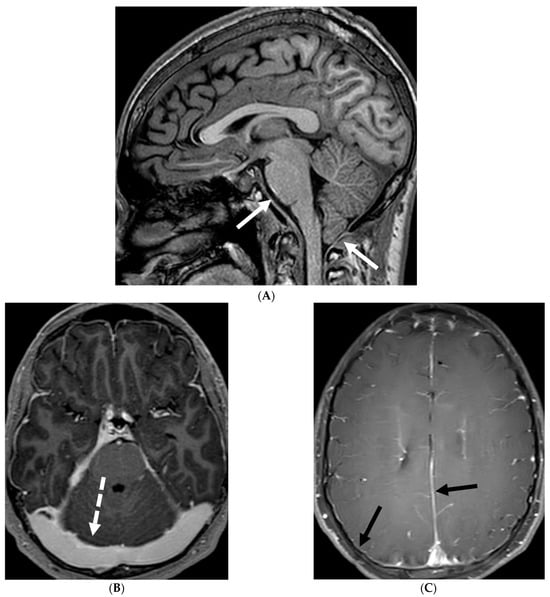

TBM is characterized by LME, predominantly smooth and localized in the basal cisterns [76]. In severe cases, this can lead to the formation of basal exudates, visible as enhancing fluid in the basal cisterns [77]. The disease is often accompanied by parenchymal abnormalities, most commonly conglomerated ring-enhancing lesions with characteristic T2 hypointensity due to caseous content, although liquefaction may cause the core to become T2 hyperintense [78]. These ring-enhancing lesions can potentially coalesce to form abscesses. TBM may also present with infarcts in the thalami or basal ganglia due to basal vasculitis (Figure 13) [78]. The meningeal involvement typically occurs through hematogenous spread, and the condition is most prevalent in children and young adults presenting with altered mental status [79]. These imaging findings along with lymphocyte predominant CSF and significantly high protein can be diagnosed as tuberculosis since culture can take weeks.

Figure 13.

Axial T1 FS (A,B) and sagittal T1 fat sat (C,D). 2-year-old girl presented with emesis, fever and status epilepticus. Septic work up revealed tubercular meningitis. Extensive abnormal enhancement is seen in the meninges, prominent in the basilar cisterns (arrows). Ring-enhancing tuberculomas are seen in the cerebellum adjacent to the fourth ventricle and in the brainstem (curved arrows). Diffuse meningeal enhancement and thickening throughout the spinal canal as well as enhancement of the nerve roots is seen (dashed arrows).